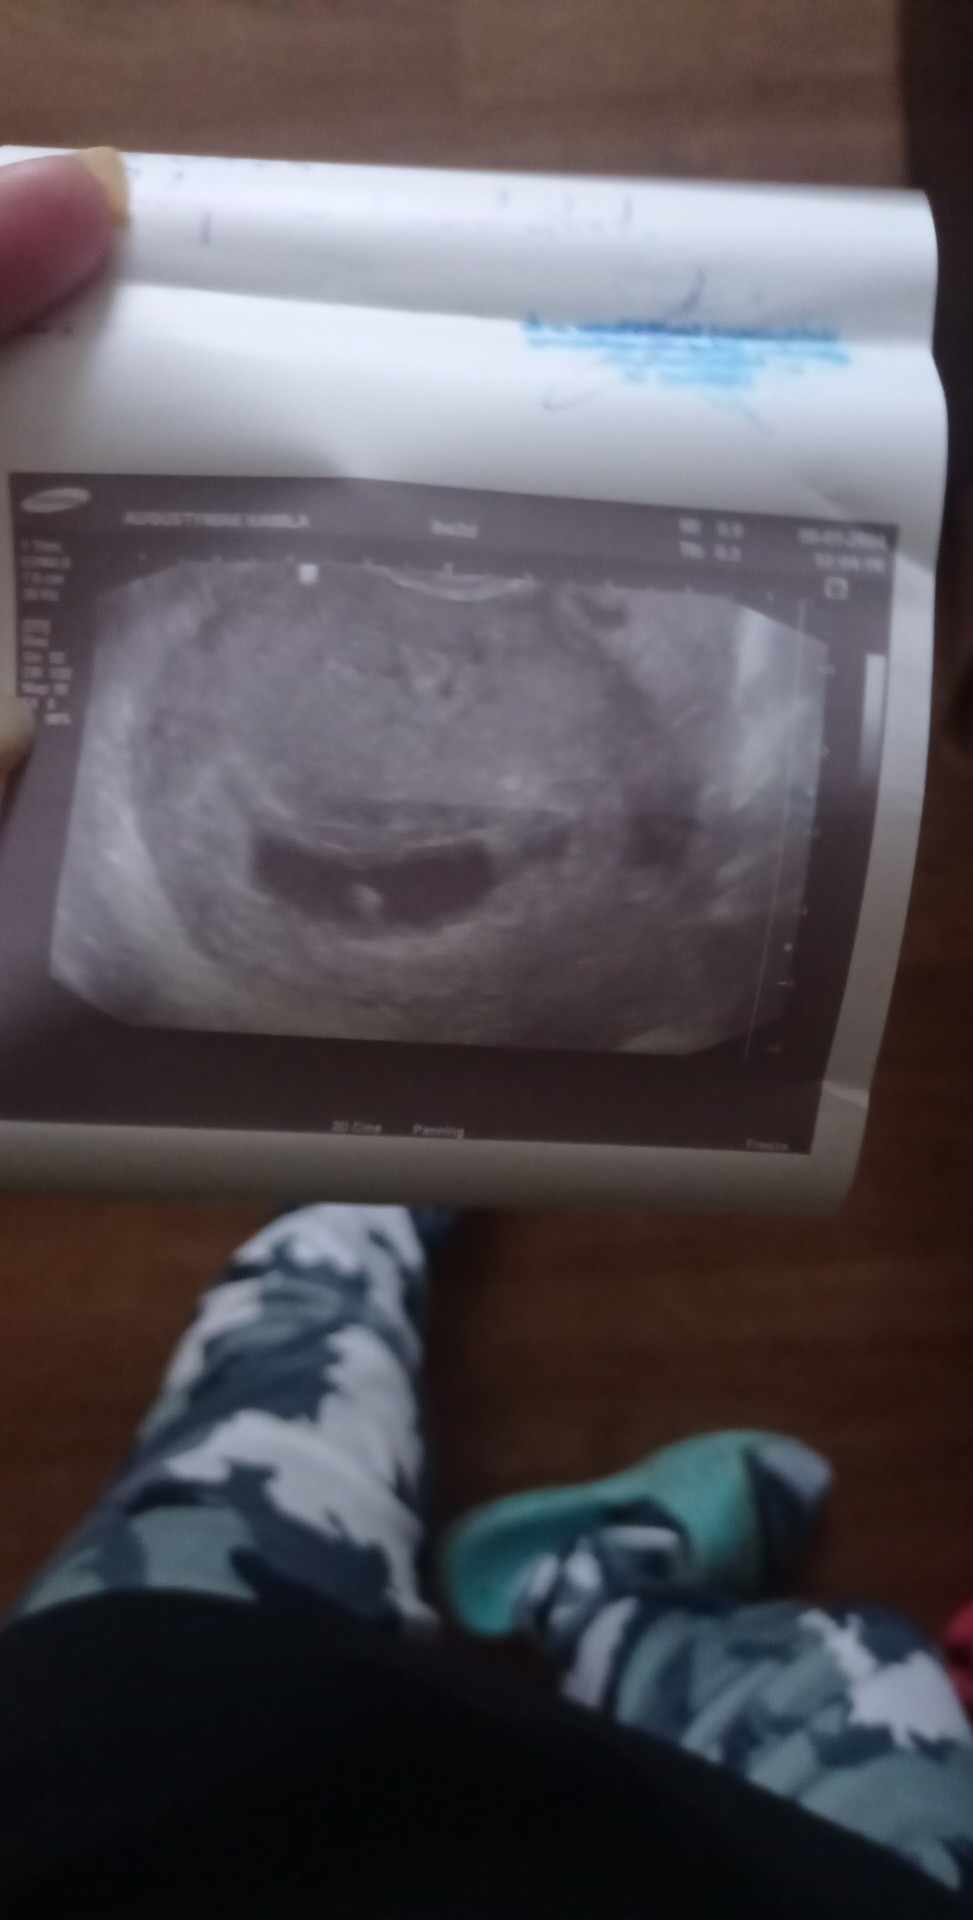

Pomóżcie proszę byłam u lekarza i stwierdził że nie widzi płodu dał skierowanie na szpital abym zrobią bete ,byłam na szpitalu ale kazali mi tydzień poczekać na wywołanie poronienia , boje się strasznie że stracę ciążę

jestem po prostu załamana nie wiem co dalej zrobić

dołączam USG .